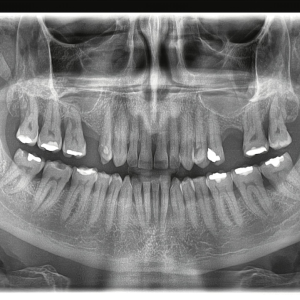

Zašto je ortopan važan u savremenoj stomatologiji?

Savremena stomatologija se oslanja na preciznu dijagnostiku. Bez kvalitetnog snimka, mnogi problemi mogu ostati neprimećeni ili se terapija ne može planirati dovoljno precizno. OPG snimak omogućava stomatologu da donese sigurniju odluku i da terapiju prilagodi stvarnom stanju u ustima pacijenta.

Kod planiranja implantata, ortodontske terapije, oralnohirurških intervencija i vađenja impaktiranih zuba, ortopan je često prvi i neophodan korak.

Ortopan snimak zuba je brz, pouzdan i veoma koristan dijagnostički pregled koji omogućava detaljan uvid u stanje zuba, vilica i okolnih struktura. Zahvaljujući panoramskom prikazu, stomatolog može preciznije da postavi dijagnozu i pravilno planira terapiju.

Ako vam je potreban pregled cele vilice, procena umnjaka, planiranje implantata ili ortodontska analiza, ortopan snimak zuba je jedan od najvažnijih prvih koraka ka tačnoj i sigurnoj dijagnostici.